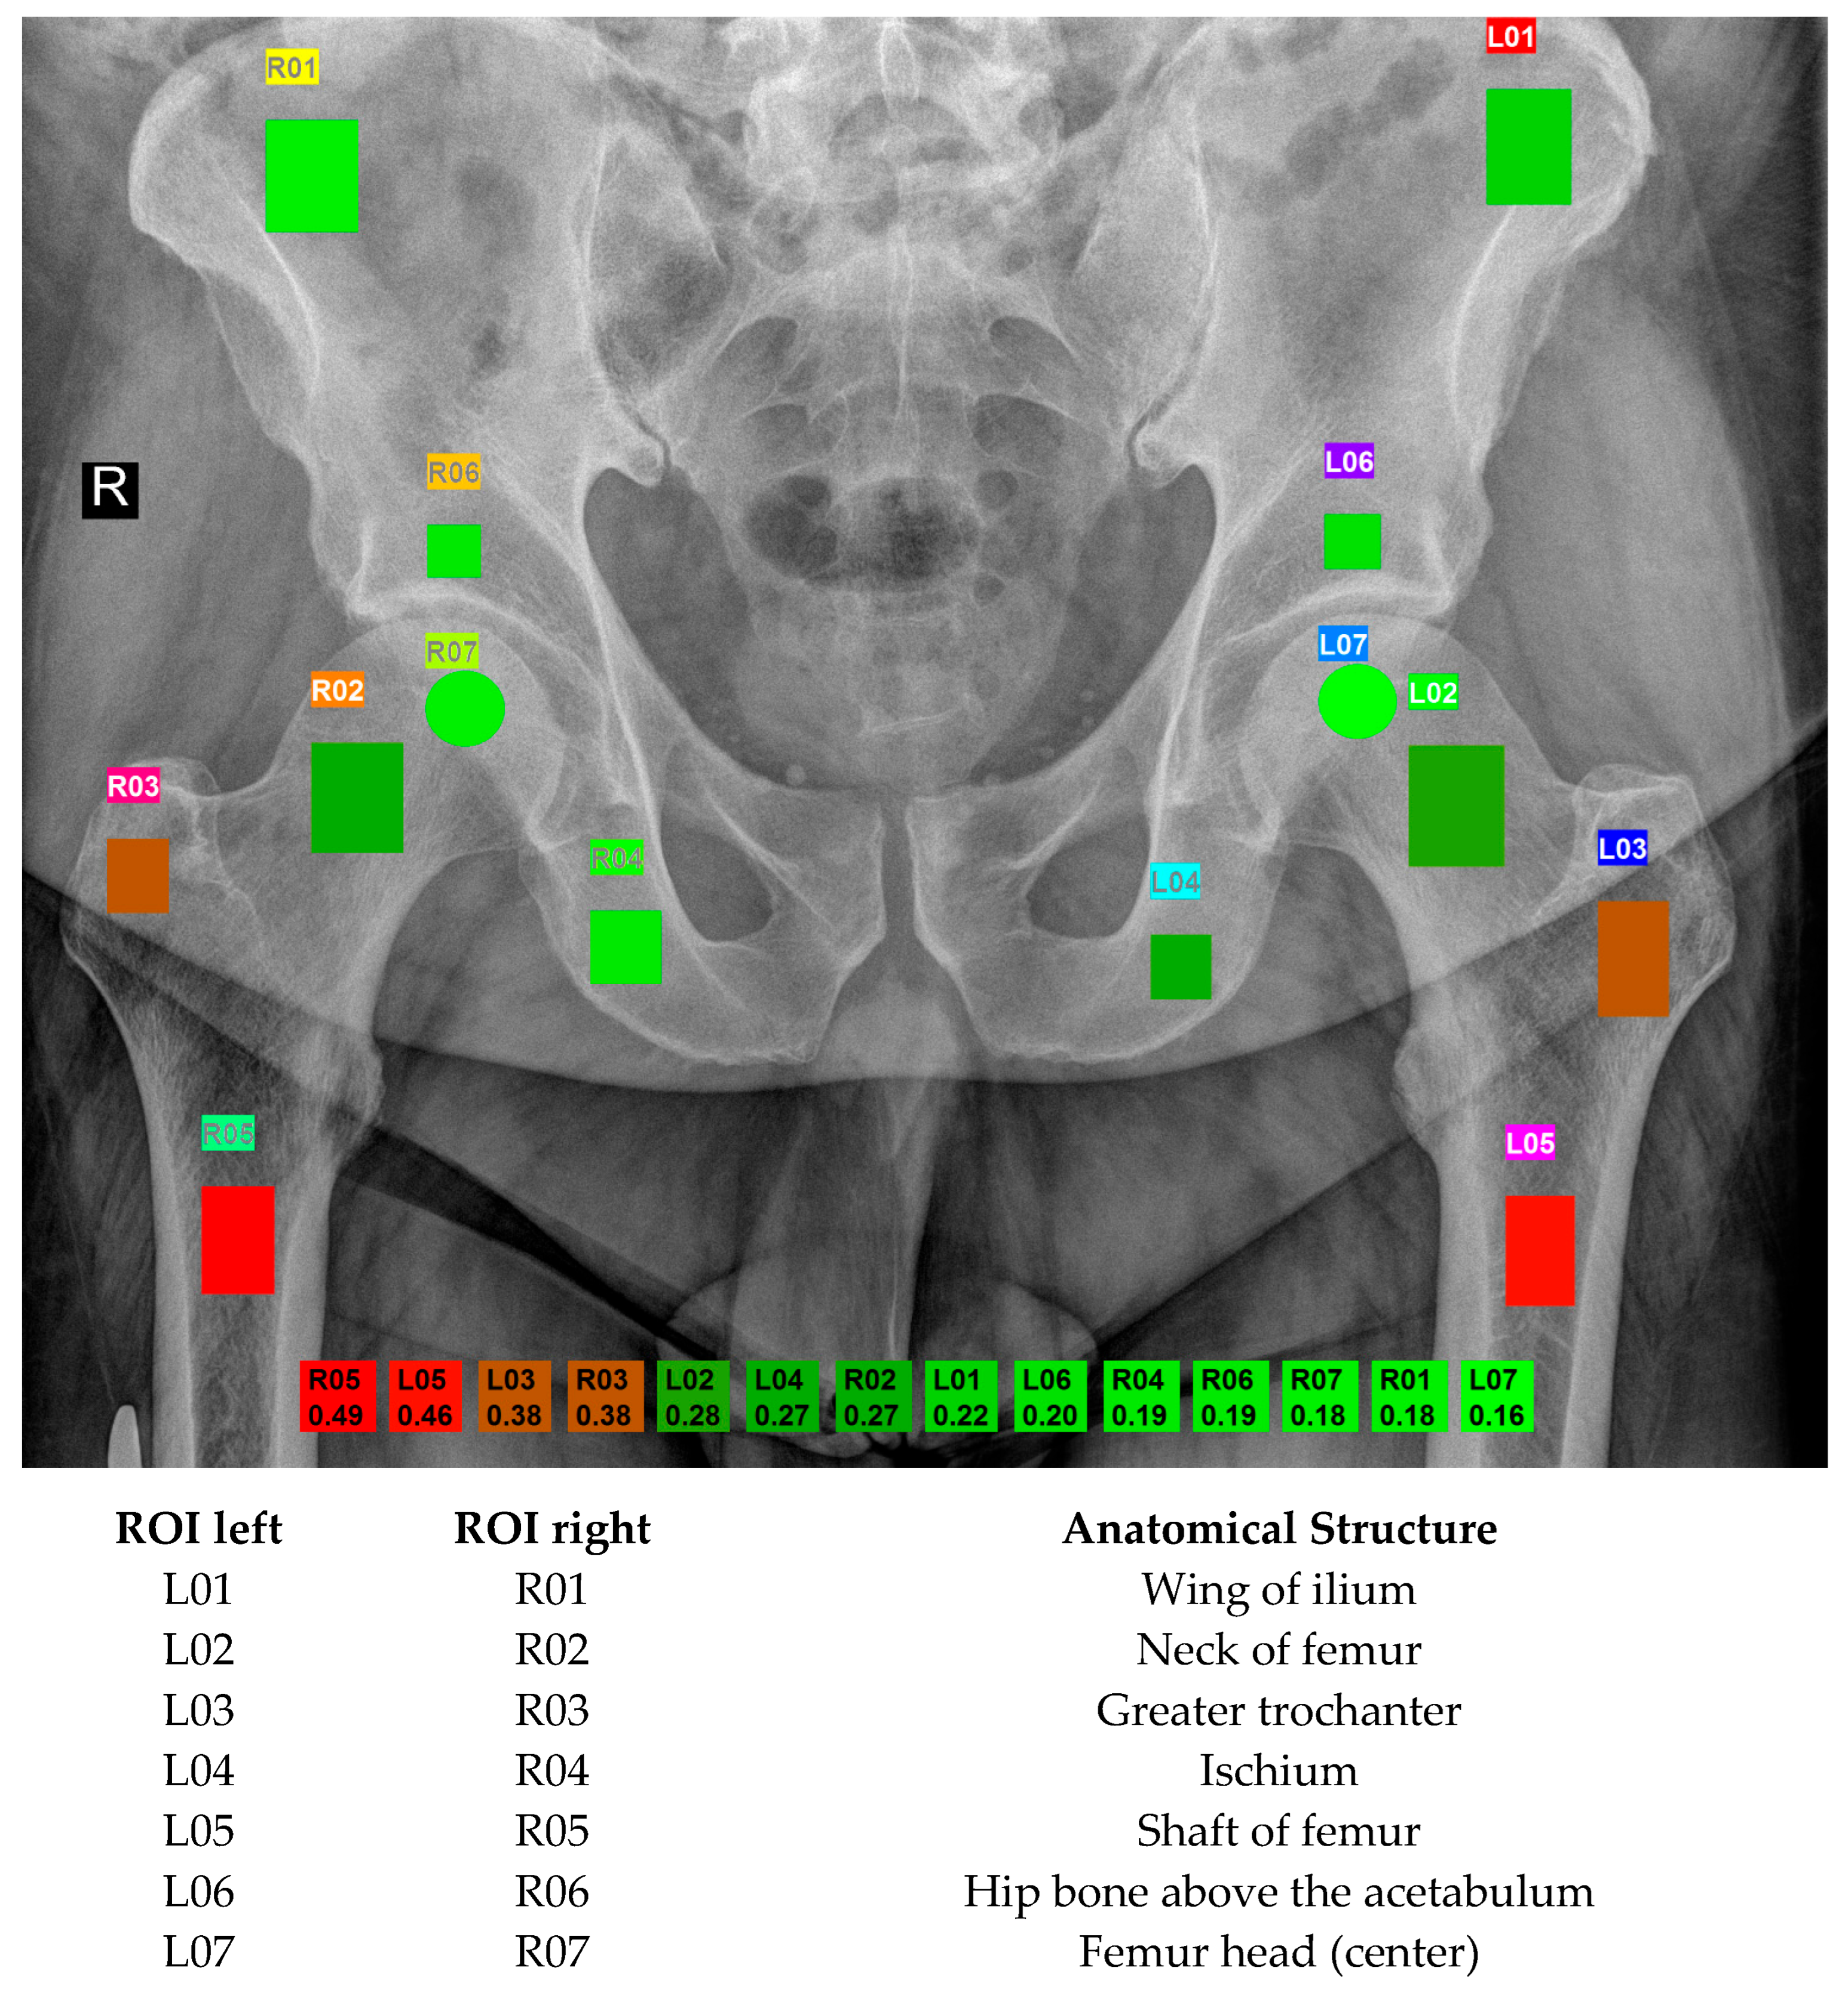

During routine examinations at the Małopolska Orthopaedic and Rehabilitation Hospital from July 2022 to February 2023, pelvic DR images were collected. This made it possible to avoid exposing the patient to an additional dose of X-ray; moreover, it allowed for collecting the chronological age, which served as the reference point for the results. These images were captured using the Visaris Avanse DR (Visaris, Serbia) and stored in DICOM (Digital Imaging and Communication in Medicine) format as 12-bit (16-bit allocated) data with a pixel spacing of 0.13256 × 0.13256 mm2. For further analysis, the images were scaled down to 8 bits by using the minimum and maximum values to establish the range. Additionally, the original images underwent further enhancement, as detailed in [12]. Each image includes twelve rectangular and two circular ROIs, carefully annotated with the assistance of MaZda 19.02 software [17] (see Figure 2 for details). Radiologists with a minimum of six years of experience in musculoskeletal structures chose those regions. The placement and the size of the ROI depended on the anatomical structure. The clinical importance and changes that occur in the bone with age dictated the choice of ROIs. Osteoporosis primarily leads to the loss of spongy bone resulting in weakened bones. ROI 01 (wing of ilium) and 04 (ischium) are areas used to assess bone quality in general and serve as reference points. ROI 02 corresponds to the femoral neck, which is standardly assessed in a densitometry examination, while ROI 03 is mainly composed of spongy bone in the greater trochanter. In turn, ROI 05 is the region of the femur where the stem of a classic hip joint endoprosthesis is stabilized. ROI 06 (hip bone above the acetabulum) is mostly cancellous bone, in which the acetabulum of the endoprosthesis is embedded and stabilized. ROI 07 represents the femoral head, susceptible to possible degenerative and necrotic changes.

The results are summarized in Table 1. The strongest correlations were observed using Pearson’s coefficient. The best-performing ROIs were the right femoral shaft (R05) and the left femoral shaft (L05), with correlation coefficients of 0.49 and 0.46, respectively. Next, a meaningful relationship was found for the greater trochanter (R03 and L03). The analysis confirmed that a moderate correlation strength (r = 0.3–0.5) was observed for several ROIs, with R05 achieving the highest correlation. All correlation coefficients presented in Table 1 are statistically significant with p ≤ 0.001. Figure 2 illustrates the Pearson correlation coefficients across all evaluated ROIs visually.

Figure 2. The figure presents manually marked regions of interests (12 rectangular and 2 circular masks) with acronyms names. The colors correspond to the Pearson’s correlation results as denoted at the bottom.